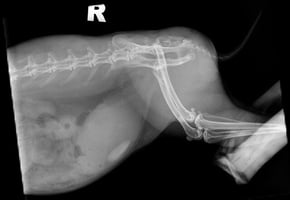

A review of intervertebral disc disease classification in dogs: a fast-changing field!

Intervertebral disc disease is a well-known condition to the veterinary surgeon in practice because ...

17 min read